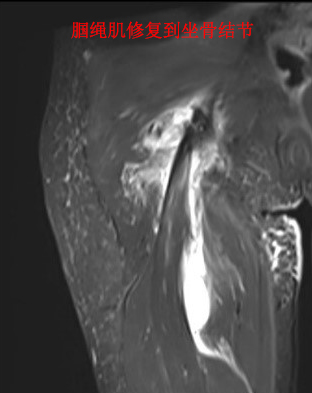

腘绳肌坐骨止点撕脱常见于短跑运动员,多发于跑步中尤其是突然用力起跑,也可发生于篮球运动起跳时。损伤后的表现是臀部疼痛,屈膝、伸髋时疼痛加重,检查可见臀部有瘀斑。我院郑州院区运动医学科黄遂柱博士团队根据小青的情况制定了科学的治疗方案。由于腘绳肌撕脱后发生肌肉回缩,肌肉断端距离坐骨结节止点大于2厘米,如果采取保守治疗则只能靠瘢痕愈合,修复慢而且术后肌肉力量会明显受影响。传统手术方案是切开手术修复撕脱的腘绳肌,但是创伤大,臀部瘢痕会给年轻爱美的女性带来不好的心理影响。为此,黄遂柱博士团队决定采取关节镜微创的手术方案,手术精准、创伤小,又不会留下令人烦恼的皮肤切口瘢痕。术中在关节镜监视下,腘绳肌被准确牢靠地修复到坐骨结节解剖位置,术后患者感到十分满意,表示没有疼痛不适。